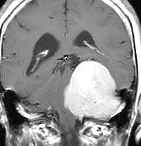

典型的な髄膜腫

この髄膜腫は中程度の大きさのものです。円蓋部髄膜種という最も多い最も手術の簡単なタイプです。麻痺や失語症やてんかんなどの症状はありません。とても美しくて若い女性の髄膜腫でしたが,子供に遺伝はしませんし,癌などと違ってタバコなどこれといった原因がなくて発生するものです。

MRIでの髄膜腫の見え方は撮影の仕方によっていろいろです。左からT1強調画像,T2強調画像,フレア画像といいます。腫瘍の横に小さく白い領域がありますが,これは脳の腫れた部分で脳浮腫といいます。髄膜腫があると周囲に脳浮腫が生じることがあります。

最も見やすいのが,ガドリニウム造影剤を注射して撮影するものです。一般的に髄膜腫は造影剤で白く映し出されます。この腫瘍は左脳側にあります。MRIの軸面という輪切りの写真では左右が逆になりますから注意してください。脳を下から見た図になっています。MRIはいろいろな方向から腫瘍を見ることができますが,右は冠状断という正面から見た図です。よく見ると腫瘍の上と下のはじっこに線状に糸を引いたように造影される部分があります。これをテールサイン(しっぽのサイン)といいます。腫瘍が硬膜に沿って延びている可能性があることを示しています。